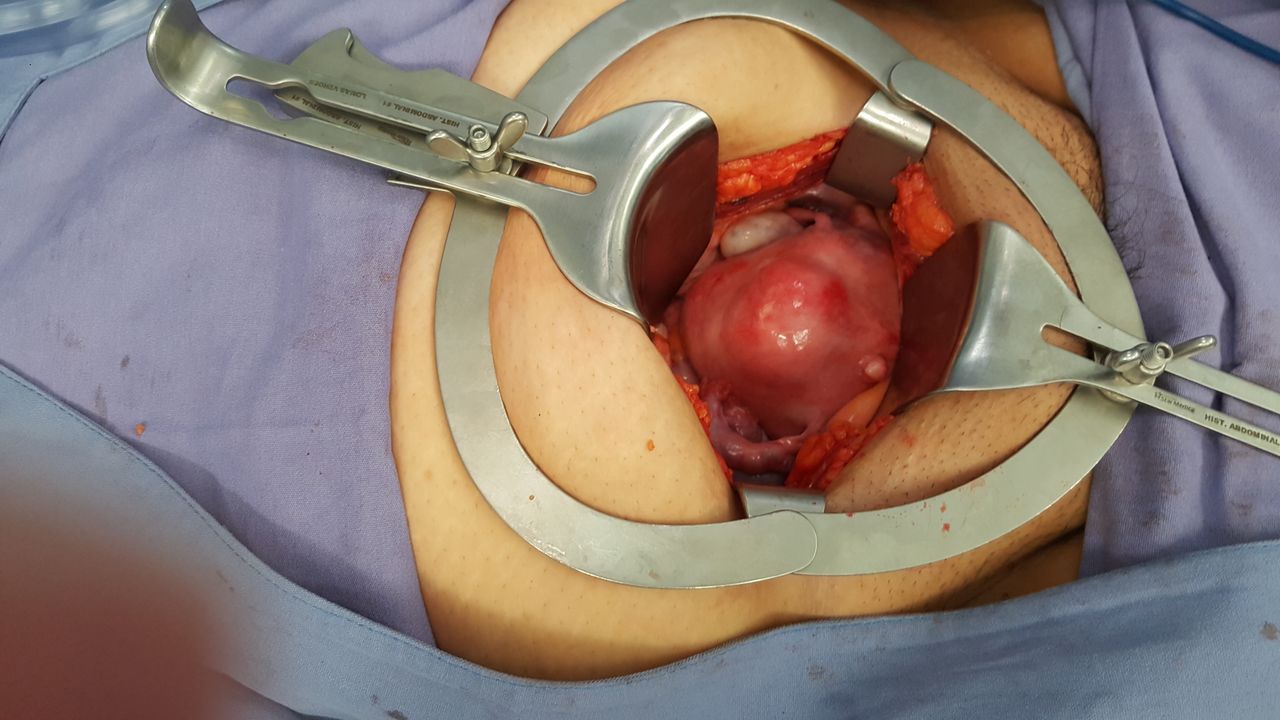

Quiero expresar mi más sincero agradecimiento al Dr. Millán. Me realizó la cirugía para retirar un fibroadenoma de aproximadamente 4 cm en mi mama izquierda y desde el primer momento me sentí en excelentes manos.

Siempre fue sumamente empático, amable y profesional, explicándome todo con calma y brindándome mucha tranquilidad durante todo el proceso. La cirugía fue impecable y cuidó muchísimo cada detalle para que la herida quedara no solo funcional, sino también estética, algo que valoro profundamente.